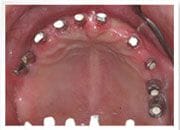

林小姐上顎微創植牙10顆